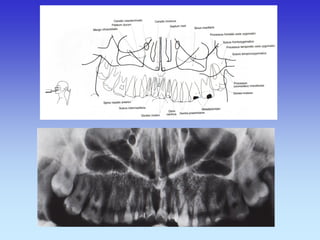

PARANAZALNI SINUSI i ORBITE

1. Frontalni sinus

CT- SINUSA

TRANSVERZALNI SLOJ

1. Etmoidni sinus 2. Sfenoidni sinus

1.Maksilarni sinus

2.Pterigoidne ploče

3.Nazofrinks

4.Nosna pregrada

CT- SINUSA TRANSVERZALNI SLOJ

2.Tvrdo nepce

3.Mandibula

4.M. maseter

CT- SINUSA KORONARNI SLOJ (od naprijed prema straga)

1. Etmoidni sinus

2. Donja nosna školjka

3. Srednjanosna školjka

CT- SINUSA KORONARNI SLOJ

2.Septum nasi

3.Orbita

1.Sfenoidni sinus

3.Prednji klinoid

KORONARNI SLOJ

1.Retroorbitalna mast

2.M. Rectus medialis

3.Leća

4.M. Rectus lateralis

5.Optički živac